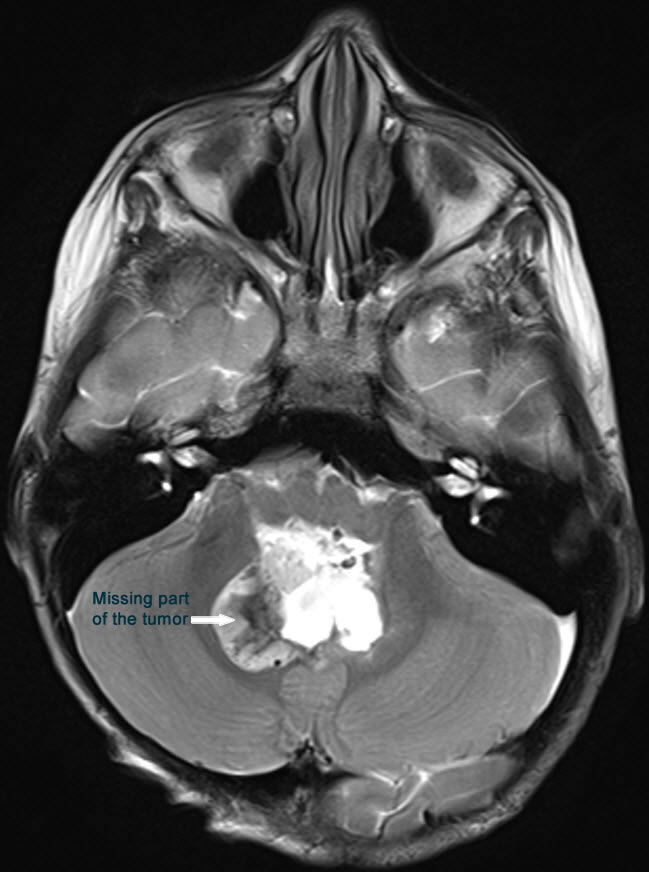

Fig-36: MRI done during surgery showing the missing part of the tumor, which was subsequently removed.

There is still part of the tumor in the right upper corner and the right foramen of Leuschko. Resection of this part was achieved until the normal cerebellar tissues were seen at these angles. Strict hemostasis with water-tight closure of the dura and bone flap was secured with 2 stitches and routine closure of the wound.